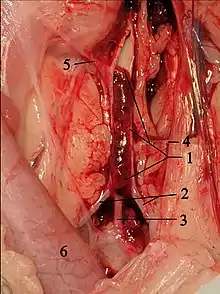

.jpg.webp)

A diagnosis of hypertrophic cardiomyopathy is based upon a number of features of the disease process. While there is use of echocardiography, cardiac catheterization, or cardiac MRI in the diagnosis of the disease, other important considerations include ECG, genetic testing (although not primarily used for diagnosis),[33] and any family history of HCM or unexplained sudden death in otherwise healthy individuals. In about 60 to 70% of the cases, cardiac MRI shows thickening of more than 15 mm of the lower part of the ventricular septum. T1-weighted imaging may identify scarring of cardiac tissues while T2-weighted imaging may identify oedema and inflammation of cardiac tissue which is associated with acute clinical signs of chest pain and fainting episodes.[34]